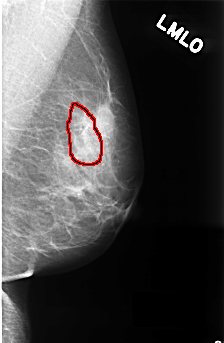

FILE: C_0335_1.LEFT_MLO.OVERLAY

TOTAL_ABNORMALITIES 1

ABNORMALITY 1

LESION_TYPE CALCIFICATION TYPE FINE_LINEAR_BRANCHING DISTRIBUTION LINEAR

ASSESSMENT 4

SUBTLETY 4

PATHOLOGY BENIGN

TOTAL_OUTLINES 1

BOUNDARY